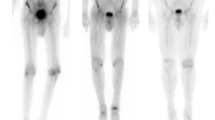

In a study by Bokhari et al. that enrolled 45 subjects (12 with AL, 16 ATTRwt, and 17 ATTRm) with cardiac amyloidosis (37 EMB proven), 99mTc-PYP SPECT was able to selectively bind to ATTR with good sensitivity and specificity. Cardiac retention was assessed using both a semiquantitative visual score (see Fig. 1) in relation to bone uptake (0 = no cardiac uptake to 3 = high uptake greater than bone) and a quantitative analysis by drawing a region of interest (ROI) over the heart corrected for contralateral counts and calculating a heart-to-contralateral ratio (H/CL). Although a cohort with AL had some tracer uptake, patients with ATTR had significantly higher semiquantitative cardiac VS as well as quantitative scores. H/CL ≥ 1.5 consistent with intensely diffuse myocardial tracer retention had 97 % sensitivity and 100 % specificity for identifying ATTR cardiac amyloidosis [24••]. In addition, the degree of cardiac tracer retention correlated with LV thickness and mass similar to prior studies with 99mTc-DPD [19••].

a–c Quantitative method of calculating the distribution of 99mTc-PYP uptake. Raw images of (a) a representative negative subject and (b) a positive subject are shown 1 h after radiotracer infusion. ROI circles are depicted in green, and the contralateral comparison circle is depicted in blue. SPECT image of (c) a patient with ATTR amyloidosis showing predominantly apical septal uptake. ROI region of interest, CL contralateral, cts counts, Std Dev standard deviation

Several points are notable in this study. First, a simple nuclear scan can distinguish ATTR from cardiac AL with good sensitivity and specificity using a quantitative method (H/CL ≥ 1.5), eliminating potential reader bias from semiquantitative methods. Second, although subjects with ATTRwt had greater LV mass and wall thickness, those with AL and ATTRm did not, and yet a H/CL was significantly higher in patients with ATTRm, suggesting that 99mTc-PYP has a unique affinity for ATTR. Finally, several limitations are worth noting. This was a small single-center study wherein no control group (left ventricular hypertrophy without amyloid) was included for comparison, so the absence of uptake may mean AL or non-amyloid heart disease. Many patients had severe phenotypes with thickened LV walls. In addition, a large percentage of patients with ATTRm had the V122I mutation which is the commonest mutation in the USA. Despite these limitations, 99mTc-PYP shows promise in detecting ATTR and is readily available in the USA.